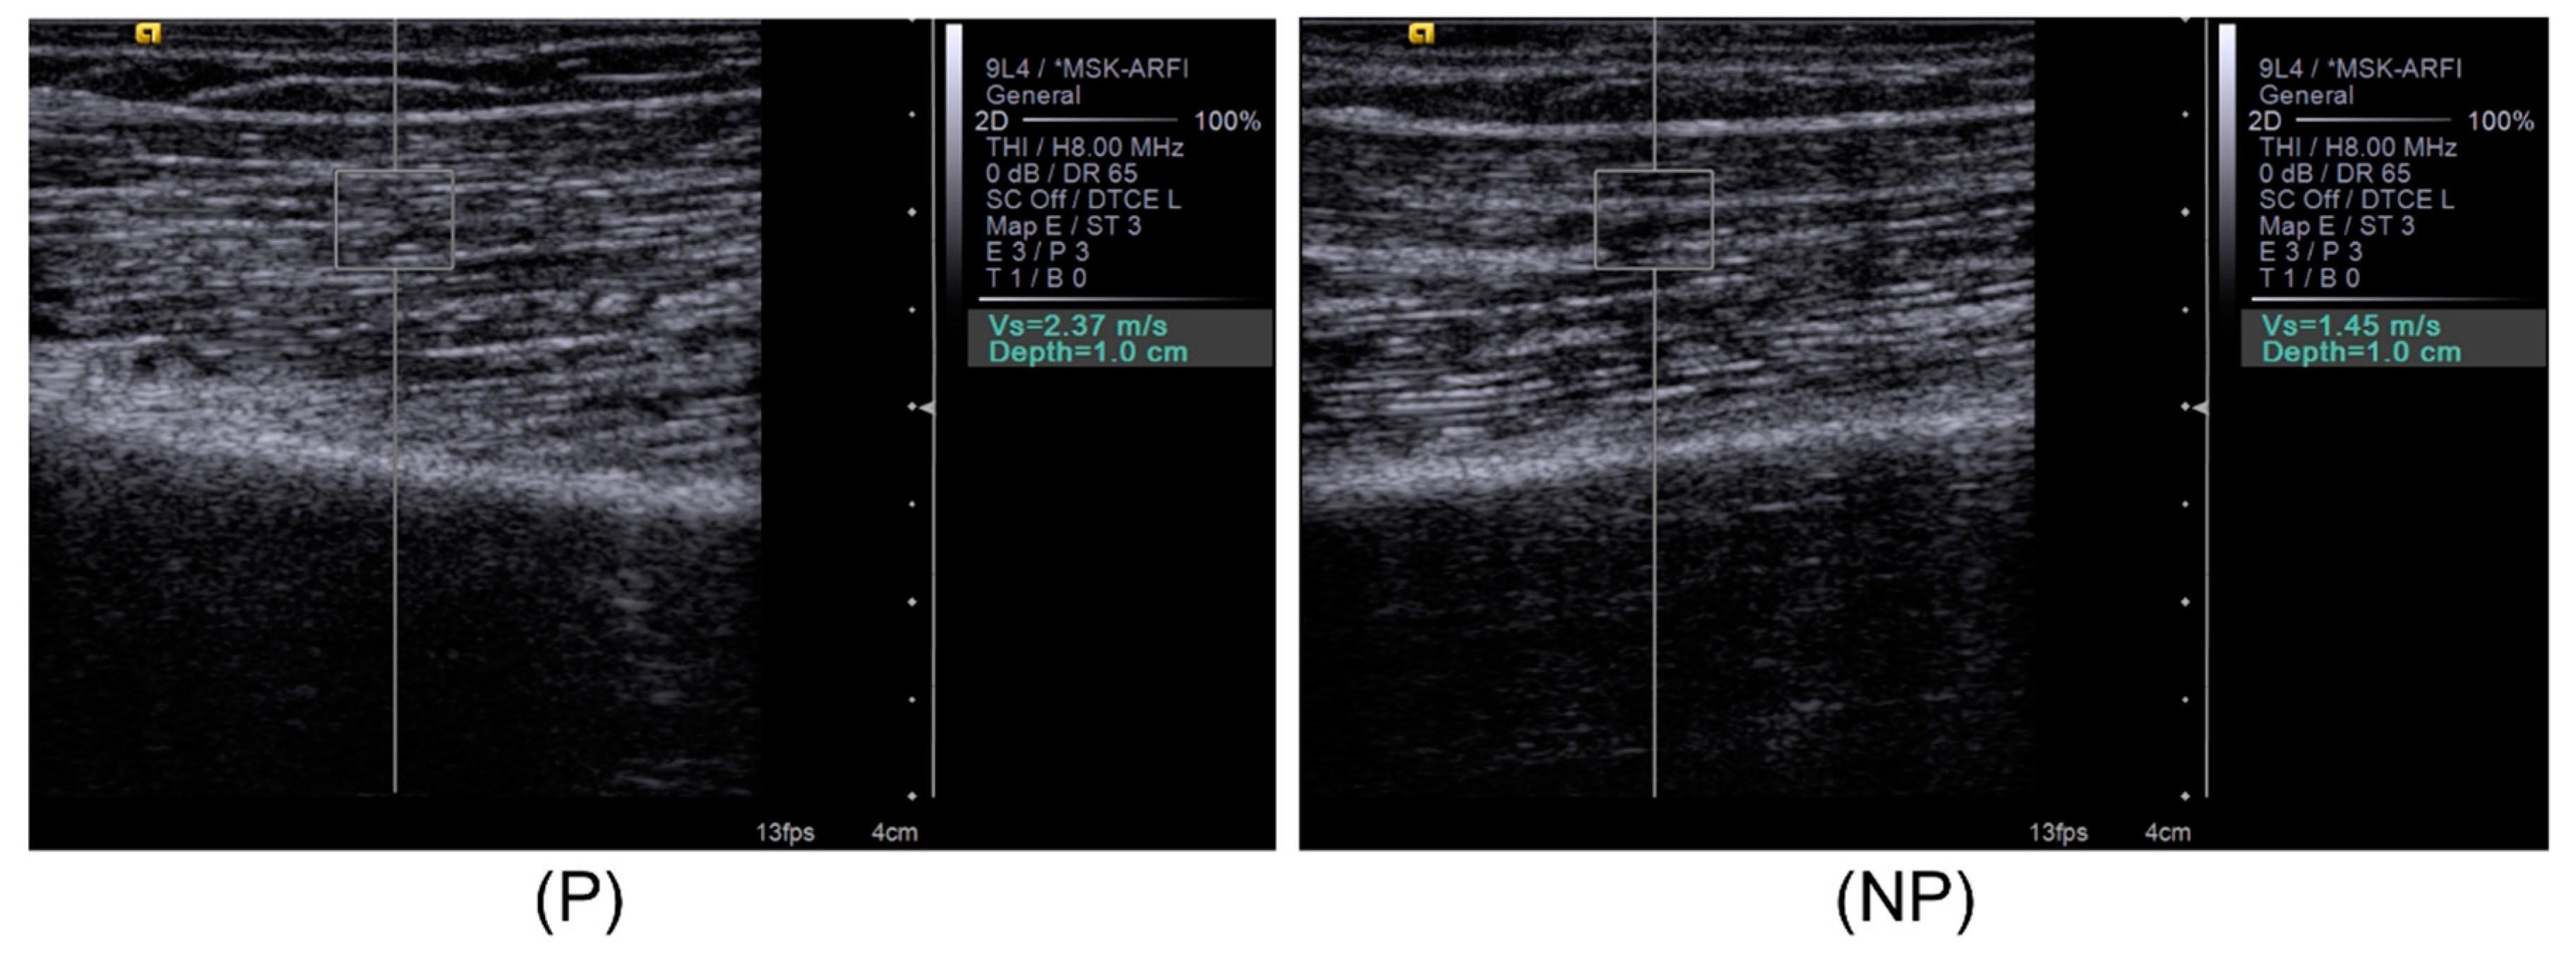

2.3. Bicep Brachii Muscle Shear Wave Velocity and Gray Scale Image Capture

2.4. Image Processing